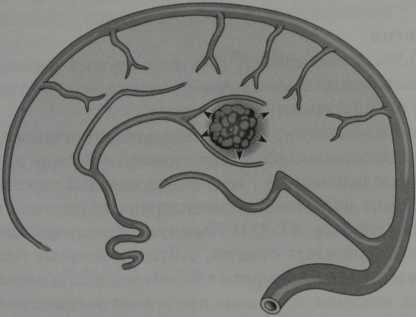

Кавернозная гемангиома (схематическое изображение). Дольковое расположение синусоидальных полостей с кровоизлияниями на разных стадиях распада. Гемангиома окружена ободком гемосидерина (стрелки).